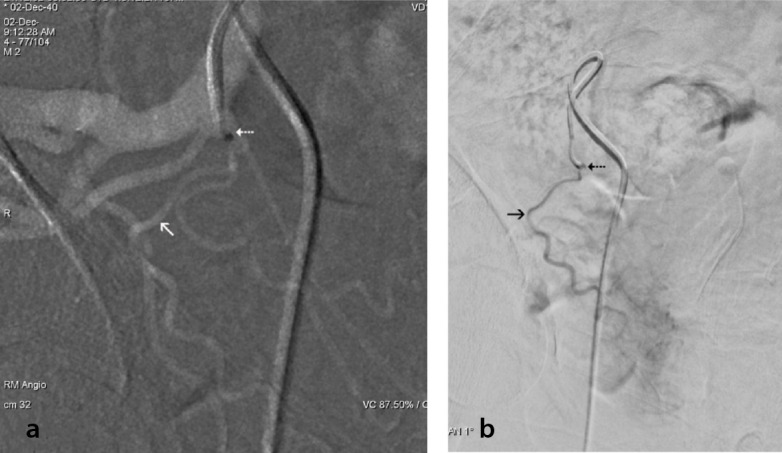

Prostatic artery (PA) origination from a common trunk with the superior vesical artery (SVA) is a frequent cause of technical difficulties in PA catheterization for PA embolization (PAE). These difficulties, which substantially increase the operative time, radiation dose, cost, and technical failure rate of PAE, can often be overcome by the utilization of a steerable microcatheter (MC) with a tip that can be manually adjusted at an angle that optimally conforms to the shape and origin of the common vesicoprostatic trunk. Adjunctive techniques that can be applied when the steerable MC fails to engage the PA include: 1) the protective temporary embolization of the SVA so that a permanent embolic can be redirected into the PA; 2) PAE via collaterals between superior vesical branches and the PA; and 3) embolization from a proximal position of the MC near the PA orifice to exploit preferential flow to the PA. In the authors' recent experience, the utilization of a steerable MC with and without adjunctive techniques (in 12 and 23 patients, respectively) resulted in a 35% increase in the technically successful embolization of PAs originating from vesicoprostatic trunks with no significant complications. Familiarization with alternative devices and techniques may substantially improve the technical outcome of PAE in cases with challenging arterial anatomy.